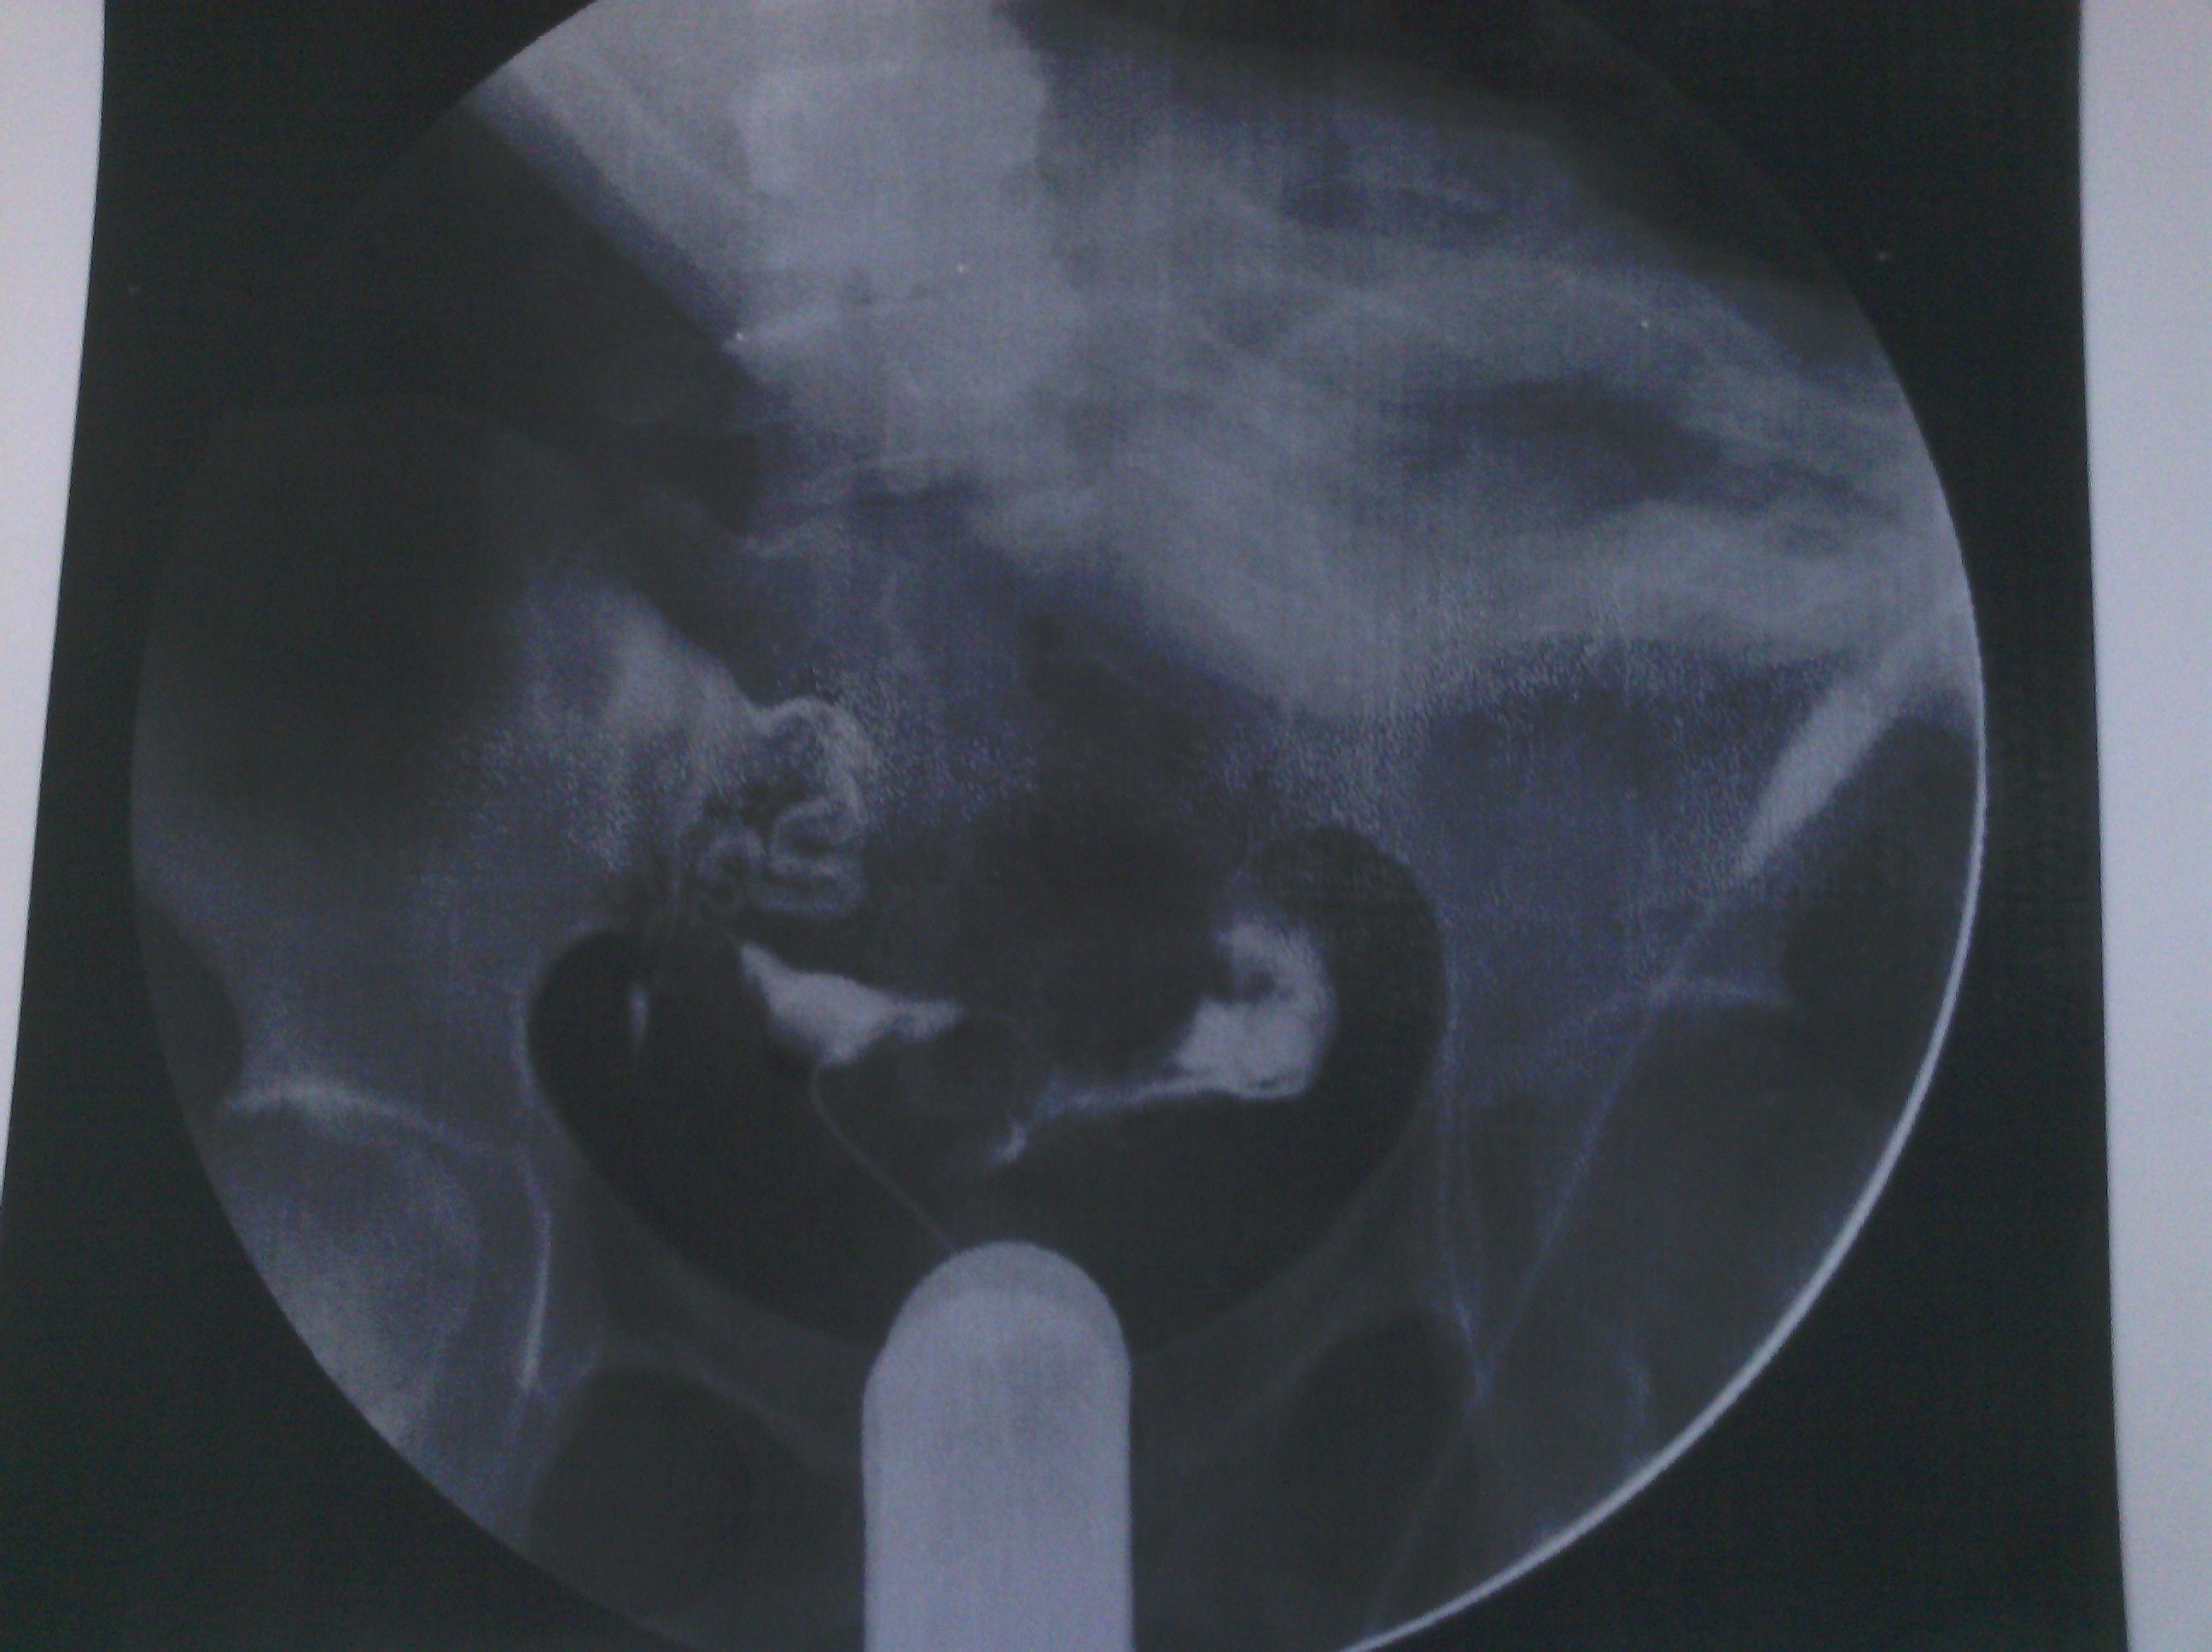

最新输卵管造影图片,麻烦各位大侠帮忙看看,纠结中 各位好,这是我11月6日做的输卵管造影图片,麻烦给看看现在是什么情况。在医院光说通而不畅有粘连,也没说哪个部位粘连,具体的是哪个部位有毛病呢?是间质部,峡部或是壶部。说少量弥散,然而弥散的片子也没延迟拍摄,是造影后直接就出来了,那判断的标准准确吗?看了好几年的病了,慕名到哪个医院去了,都没给过我合理化的建议,都是到哪家,哪家哪个拿手就推荐你做哪个,我现在看见医院两个字就想吐。我就是想,死,我也得死个明白。麻烦各位好心人看看我的片子给我一个合理化建议。现在的输卵管造影是个什么情况应该怎样治疗,在此拜谢各位了。我没啥财富值,对不起各位了。望能看片子解释一二,不胜感激。 点击展开 母婴用户710320885 2013-11-09 08:05 为您推荐: 其他回答 片子没标左右 所以我不清楚是哪边。 可以告诉你的是 面对我左边的输卵管走形上举,有黏连。面对右边的输卵管扭曲扩张。整个状况不是很乐观,具体治疗请咨询妇产科医生。 匿名用户 2013-11-11 14:28 相关问题 求讲解输卵管造影图片 妇科医生专家好:请帮忙看看这份“子宫输卵管造影检查报告”: 帮忙看看造影的报告,双侧输卵管炎不能怀孕了吗?

各位好,这是我11月6日做的输卵管造影图片,麻烦给看看现在是什么情况。在医院光说通而不畅有粘连,也没说哪个部位粘连,具体的是哪个部位有毛病呢?是间质部,峡部或是壶部。说少量弥散,然而弥散的片子也没延迟拍摄,是造影后直接就出来了,那判断的标准准确吗?看了好几年的病了,慕名到哪个医院去了,都没给过我合理化的建议,都是到哪家,哪家哪个拿手就推荐你做哪个,我现在看见医院两个字就想吐。我就是想,死,我也得死个明白。麻烦各位好心人看看我的片子给我一个合理化建议。现在的输卵管造影是个什么情况应该怎样治疗,在此拜谢各位了。我没啥财富值,对不起各位了。望能看片子解释一二,不胜感激。